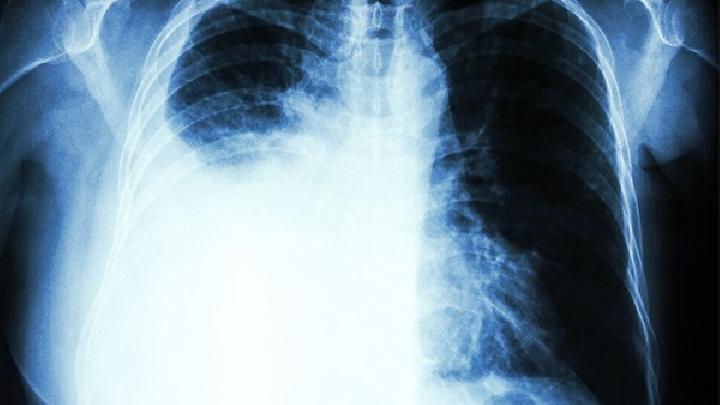

肺纤维化是一种很常见的呼吸系统的疾病,由于这种疾病的危害比较大,严重影响着患者的健康,而且很多打算要孩子的患者听说这种疾病会遗传,都内心比较恐慌,迟迟不敢怀孕,那么,肺纤维化有遗传性吗?我们从肺纤维化的病因入手了解一下吧。

肺纤维化起病隐匿,进行性加重,表现为进行性气急,干咳少痰或少量白黏痰,晚期出现以低氧血症为主的呼吸衰竭,所以肺纤维化的治疗很关键,那么,肺纤维化到哪治疗?如何选择治疗医院呢?下面大家一起来了解一下吧。

怎样查出肺纤维化呢?肺纤维化这种疾病越早治疗效果越好,如果发展到晚期很可能发生更多的并发症,甚至是生命危险,那么患者就要尽早的发现病情尽早的进行肺纤维化的检查和治疗,那么具体检查哪些内容可以进行肺纤维化的诊断呢?